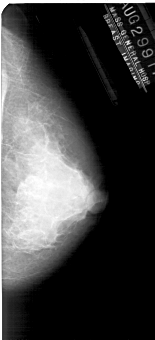

A_1927_1.RIGHT_CC

RIGHT_CC LINES 5086 PIXELS_PER_LINE 2311 BITS_PER_PIXEL 12 RESOLUTION 43.5 NON_OVERLAY